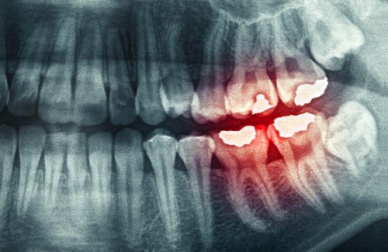

Sur le long terme, serrer ou grincer des dents peut provoquer :

- Des problèmes dans l’articulation temporo-mandibulaire.

- Des inflammations centrées sur les muscles de cette zone.

- Une usure prématurée des dents.

- Des fractures dentaires.

- La perte de l’émail dentaire.

- Une sensibilité excessive des dents.